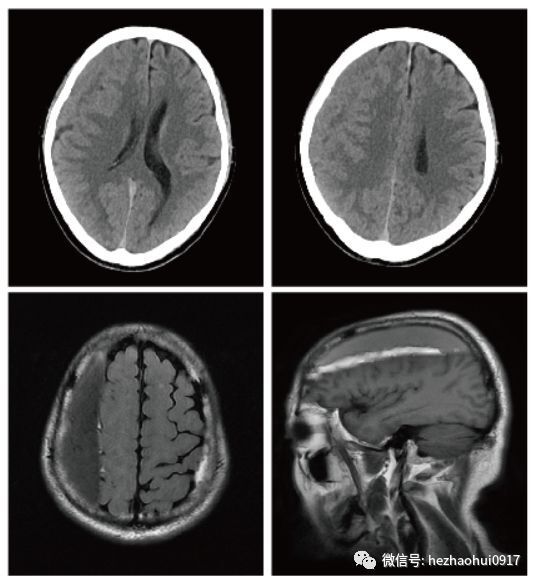

病情簡介: 患者為65歲男性,因“跌倒后頭暈2月”入院。入院前2月曾有輕微頭部外傷史?;颊咭浴奥杂材は卵[”收入我科住院治療。 既往史:肺結(jié)核病史2年。 輔助檢查: 術(shù)前頭部CT及MRI平掃: 診斷: 1.雙側(cè)慢性硬膜下血腫(右側(cè)額頂部;左側(cè)枕部) 2.原發(fā)性高血壓2級 很高危 3.陳舊性肺結(jié)核 手術(shù):右側(cè)額頂部慢性硬膜下血腫鉆孔沖洗引流術(shù) 術(shù)后CT平掃: 患者感謝信: 點(diǎn)評: 慢性硬膜下血腫是神經(jīng)外科常見的普通疾病之一,診治過程簡單,手術(shù)難度不大。這期公眾號之所以選擇發(fā)布這個(gè)病例,是因?yàn)樽罱覀冡t(yī)療組的一個(gè)病員在出院的時(shí)候給我們寫了一封感謝信,讓我聯(lián)想到我自己的一次就診經(jīng)歷,一時(shí)感慨萬千,忍不住想和大家聊一聊醫(yī)療中的人文關(guān)懷。 前不久,我的兒子咳嗽、發(fā)燒、嘔吐,我們一家人帶著他半夜十二點(diǎn)鐘到某醫(yī)院看病。非常不幸,從進(jìn)大門的保安開始,到分診護(hù)士,到收費(fèi)員,到看病醫(yī)生,到檢驗(yàn)科,到放射科,所有人的臉上都寫著四個(gè)字:麻木、冷漠,在一群小病人的哭鬧聲中,他們的嘴臉在白大褂的反襯下更顯得丑陋而猙獰。整個(gè)就診經(jīng)歷給我留下了極其惡劣的印象,當(dāng)時(shí)就一個(gè)沖動———想打人。 回過頭來看我們這個(gè)病例,感謝信中提到的黃豪醫(yī)生和張萍護(hù)士只是普通的小醫(yī)生和小護(hù)士,病人被感動到抱著他們流淚,不光是因?yàn)槭中g(shù)做得好,更是因?yàn)樗@種徹夜未眠反復(fù)到床旁觀察的責(zé)任心。醫(yī)生的專業(yè)水平固然重要,但人文精神同樣不可或缺。美國醫(yī)學(xué)博士特魯多(1848-1915)的墓志銘上寫著:“有時(shí),去治愈;常常,去幫助;總是,去安慰”。治療并不僅僅意味著治愈某種疾病,更重要的是體恤和減輕患者痛苦,關(guān)注患者體驗(yàn)。 如果能夠讓病人感受到醫(yī)護(hù)的尊重與關(guān)懷,理性地理解疾病并接受治療,醫(yī)患關(guān)系可能會更好?,F(xiàn)在的醫(yī)患關(guān)系很緊張,原因是多方面的,而醫(yī)護(hù)的人文關(guān)懷絕對是維護(hù)醫(yī)患關(guān)系最重要的因素之一。作為一個(gè)醫(yī)護(hù)工作者,我們是醫(yī)患關(guān)系最直接的參與者,同時(shí)也代表著各自工作的醫(yī)院,更是代表著醫(yī)護(hù)這個(gè)群體,就象每一個(gè)中國人代表的是中國一樣。我們每一個(gè)人都應(yīng)該從小我做起,充分踐行醫(yī)護(hù)的人文關(guān)懷,這樣才能減輕病患痛苦,維護(hù)醫(yī)生形象,改善醫(yī)患關(guān)系。 何朝暉簡介 神經(jīng)外科學(xué)博士、留美博士后、教授、主任醫(yī)師、碩士研究生導(dǎo)師、中共黨員。 任職情況: 國家衛(wèi)生計(jì)生委出血性卒中外科專業(yè)委員會常務(wù)委員。 國家衛(wèi)生計(jì)生委腦卒中防治委員會中青年委員。 中華中青年神經(jīng)外科醫(yī)師交流協(xié)會副會長,重慶地區(qū)會長。 重慶市醫(yī)學(xué)會神經(jīng)外科專業(yè)委員會腦血管外科手術(shù)學(xué)組委員。 國家自然科學(xué)基金委評議人。 《Behavioural Neurology》、 《BioMed Research International》、《Brain Research》、《Current Drug Targets》、《Neural Regeneration Research》、《Neurological Research》、《Chinese Neurosurgical Journal》、《重慶醫(yī)科大學(xué)學(xué)報(bào)》、《現(xiàn)代醫(yī)藥衛(wèi)生》審稿專家。 臨床工作方向: 出血性或缺血性腦血管疾?。ㄈ顼B內(nèi)動脈瘤、腦血管畸形、高血壓性腦出血、腦動脈硬化、腦供血不足、腦缺血、腦梗塞、頸動脈斑塊伴狹窄、煙霧病等)、腦腫瘤、顱腦外傷等。 擅長手術(shù): 顱內(nèi)動脈瘤瘤頸夾閉術(shù)、腦血管畸形切除術(shù)、頸動脈內(nèi)膜剝脫術(shù)、顱內(nèi)外血管搭橋術(shù)、腦腫瘤切除術(shù)等。 主持課題: 國家級課題3項(xiàng),省部級課題2項(xiàng),廳局級課題1項(xiàng),校級課題1項(xiàng),課題總經(jīng)費(fèi)100余萬。 發(fā)表論文: 共60余篇。SCI論文10余篇,其中《Stroke》(影響因子6.468)論著1篇,《Experimental Neurology》(影響因子4.645)論著1篇,合計(jì)影響因子約30分。 參編教材:1部;參編專著:2部。 教學(xué): 培養(yǎng)研究生30余名。 聯(lián)系方式: 微信公眾號:何朝暉腦科 好大夫在線:hezhaohuicqmu